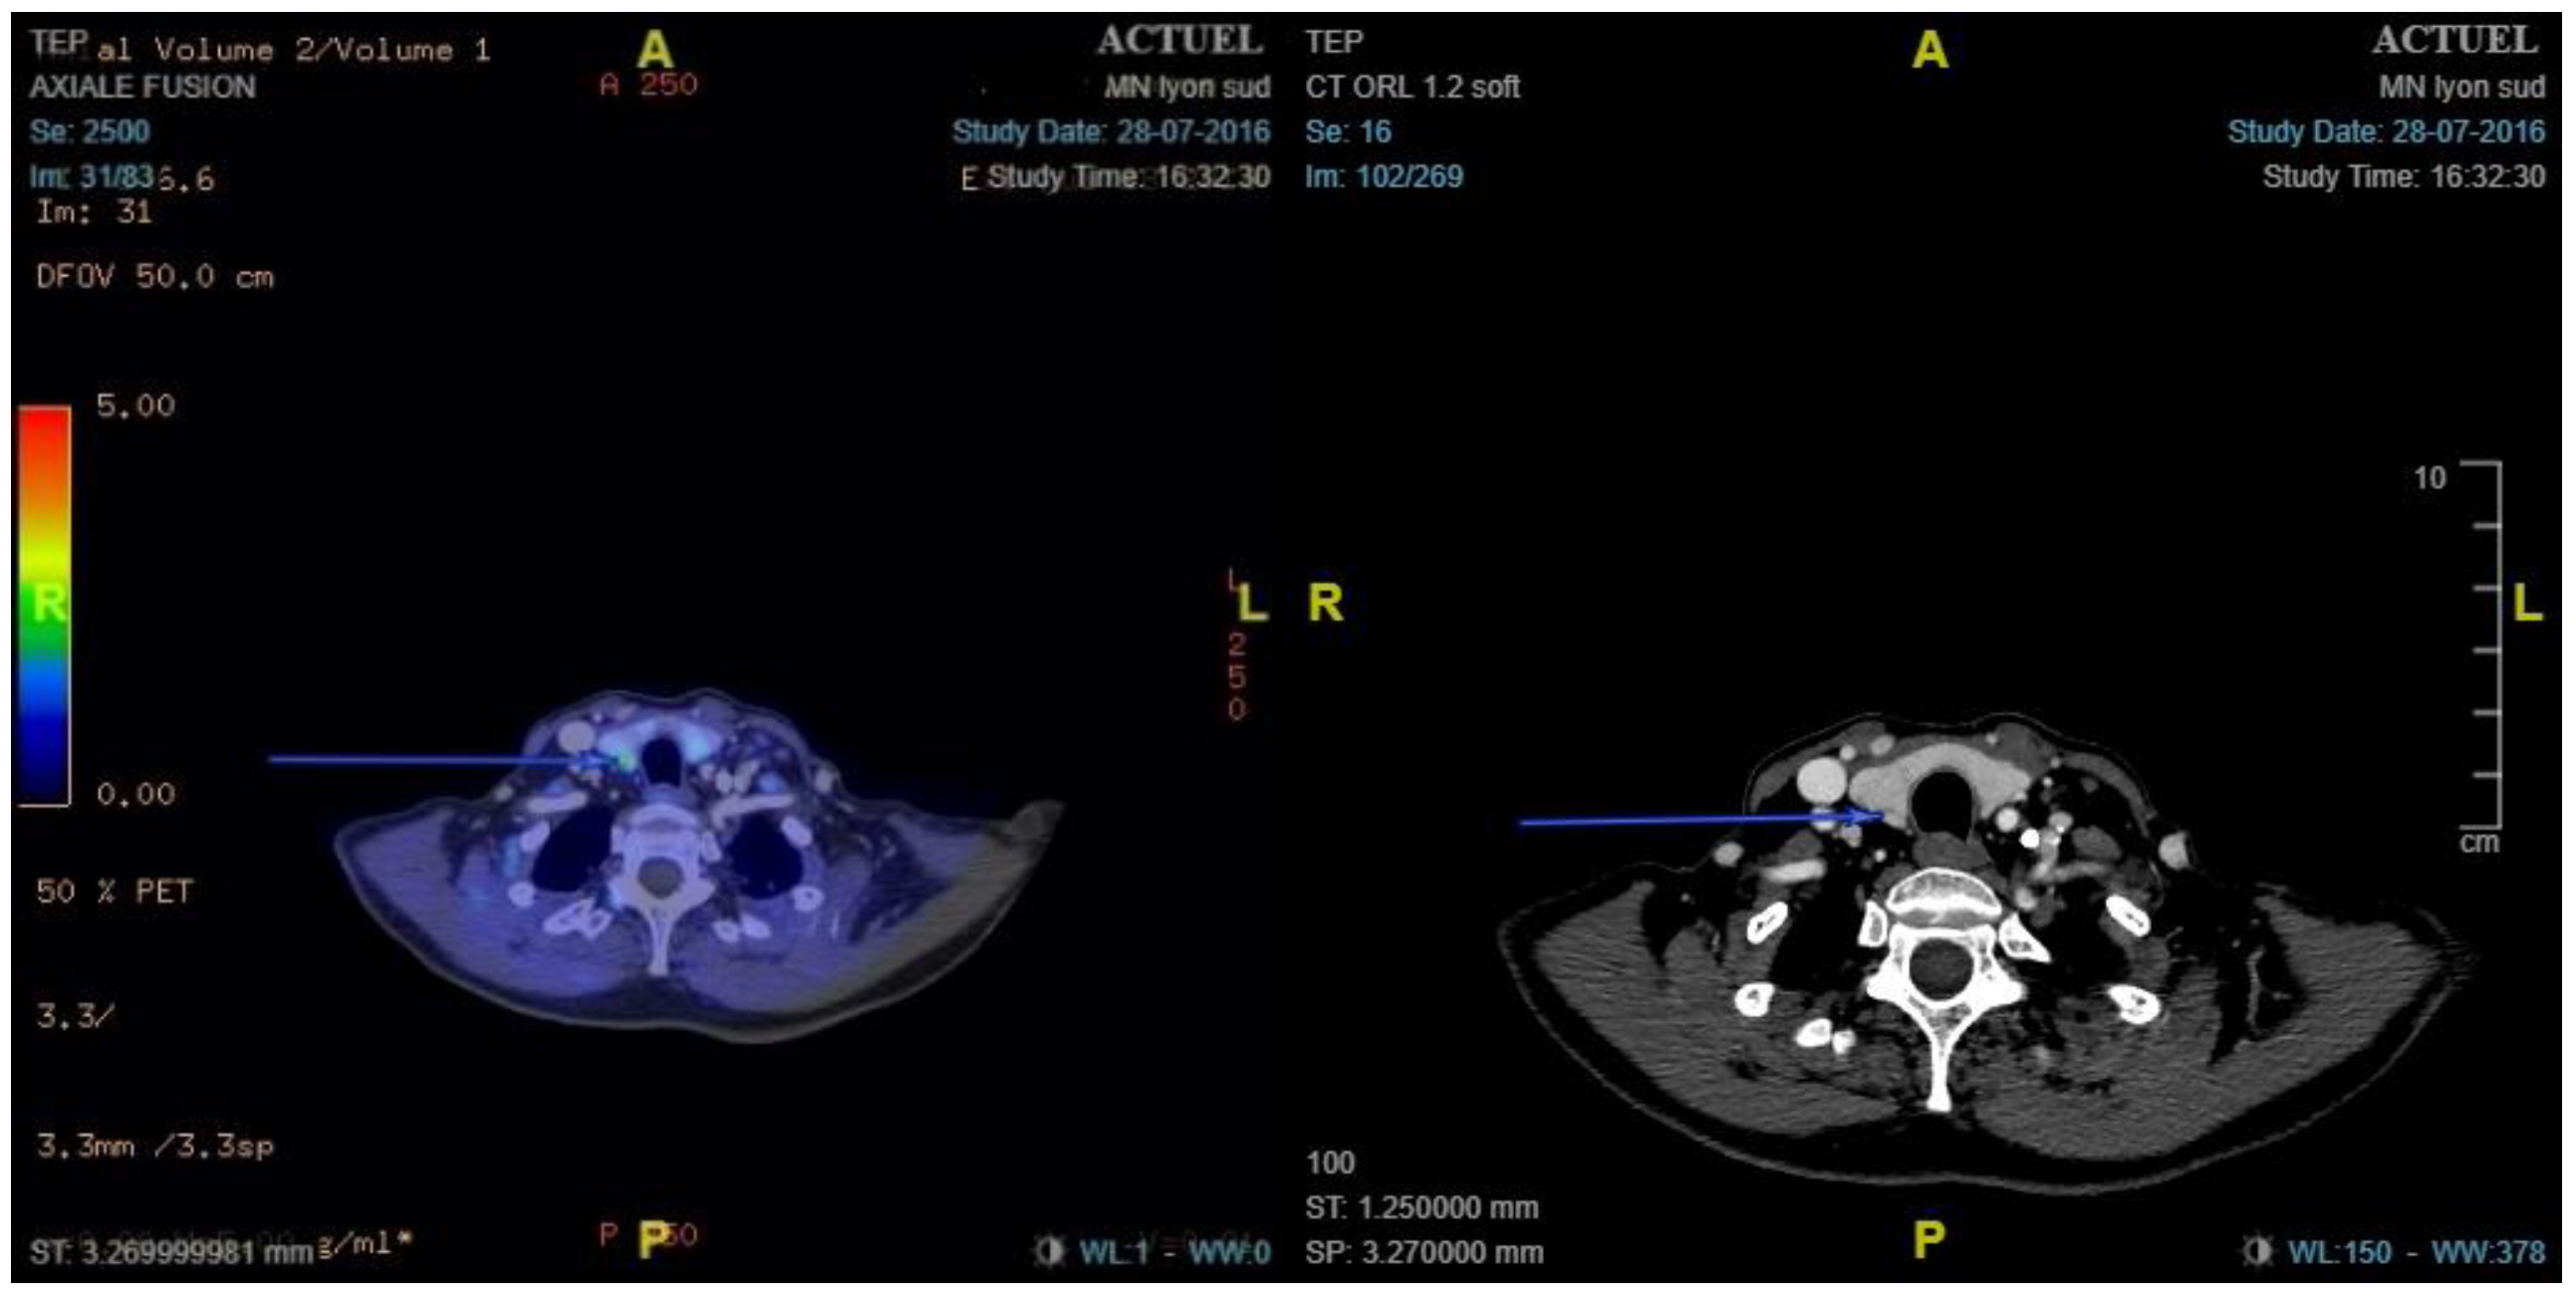

- Preoperative 18F-choline PET/ceCT data: lesion location, number of lesions, lesion size, and maximum standardised uptake value (SUVmax)

2.3.1. 18F-Choline PET/ceCT Protocol